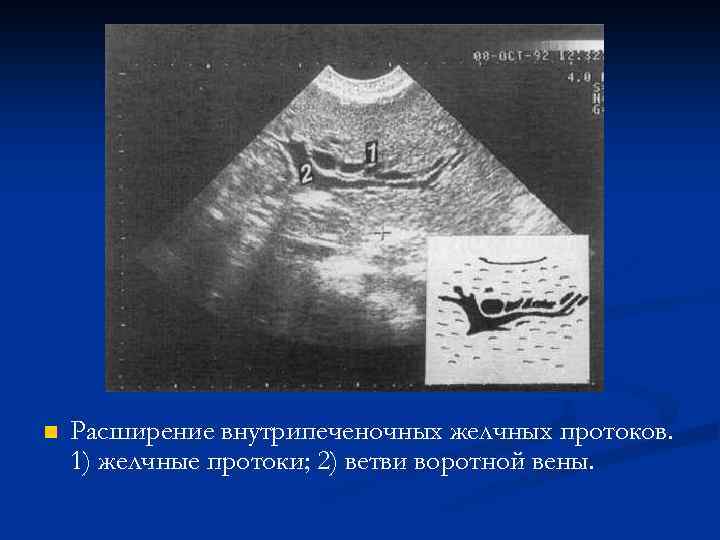

n Расширение внутрипеченочных желчных протоков. 1) желчные протоки; 2) ветви воротной вены.

n Расширение внутрипеченочных желчных протоков. 1) желчные протоки; 2) ветви воротной вены.